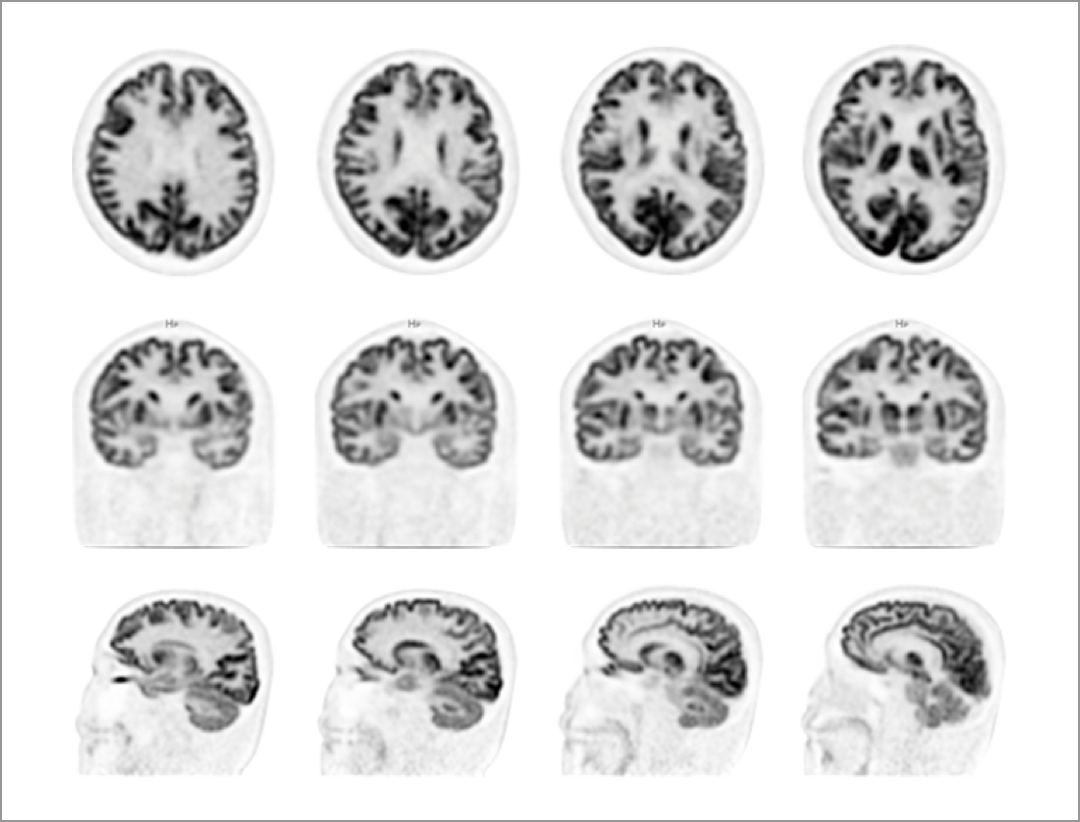

Head Motion Correction

Without the requirement for external devices, the data-driven motion correction algorithm detects motion from list-mode data during patient scans and corrects motion blurring accordingly.